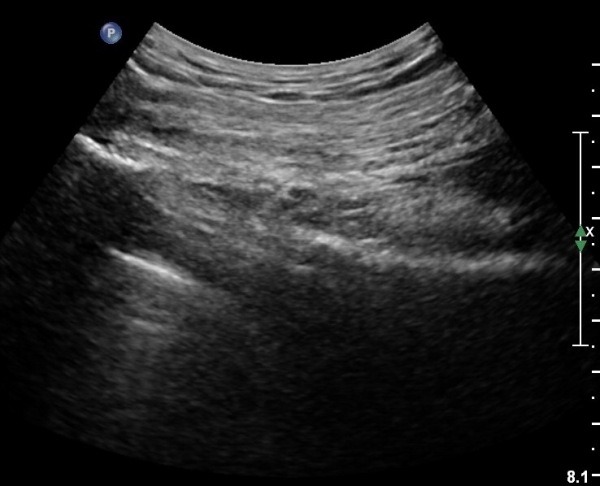

ŽÃËÀÚ¸¦ ´ëÀüÀÚ°¡ º¸À̵µ·Ï ¿ÜÃøÀ¸·Î À̵¿Çϸé Á°ñÇ¥Ãþ¿¡ ´ëÀüÀÚ·Î ÁÖÇàÇÏ´Â ÀÛÀº ³×°³ÀÇ ±ÙÀ°ÃþÀÌ °üÂûµÇ´Âµ¥ ¸Ó¸®ÂÊ¿¡¼­ ¾Æ·¡·Î SG, OI, IG, QF¸¦ °üÂûÇÒ ¼ö ÀÖ°í, ÀÌ ±ÙÀ°µé Ç¥Ãþ¿¡¼­ °í¿¡ÄÚ·Î °üÂûµÇ´Â Ÿ¿øÇü ±¸Á¶¹°ÀÌ Á°ñ½Å°æÀÌ´Ù(»çÁø 4, 5, 6, 7).